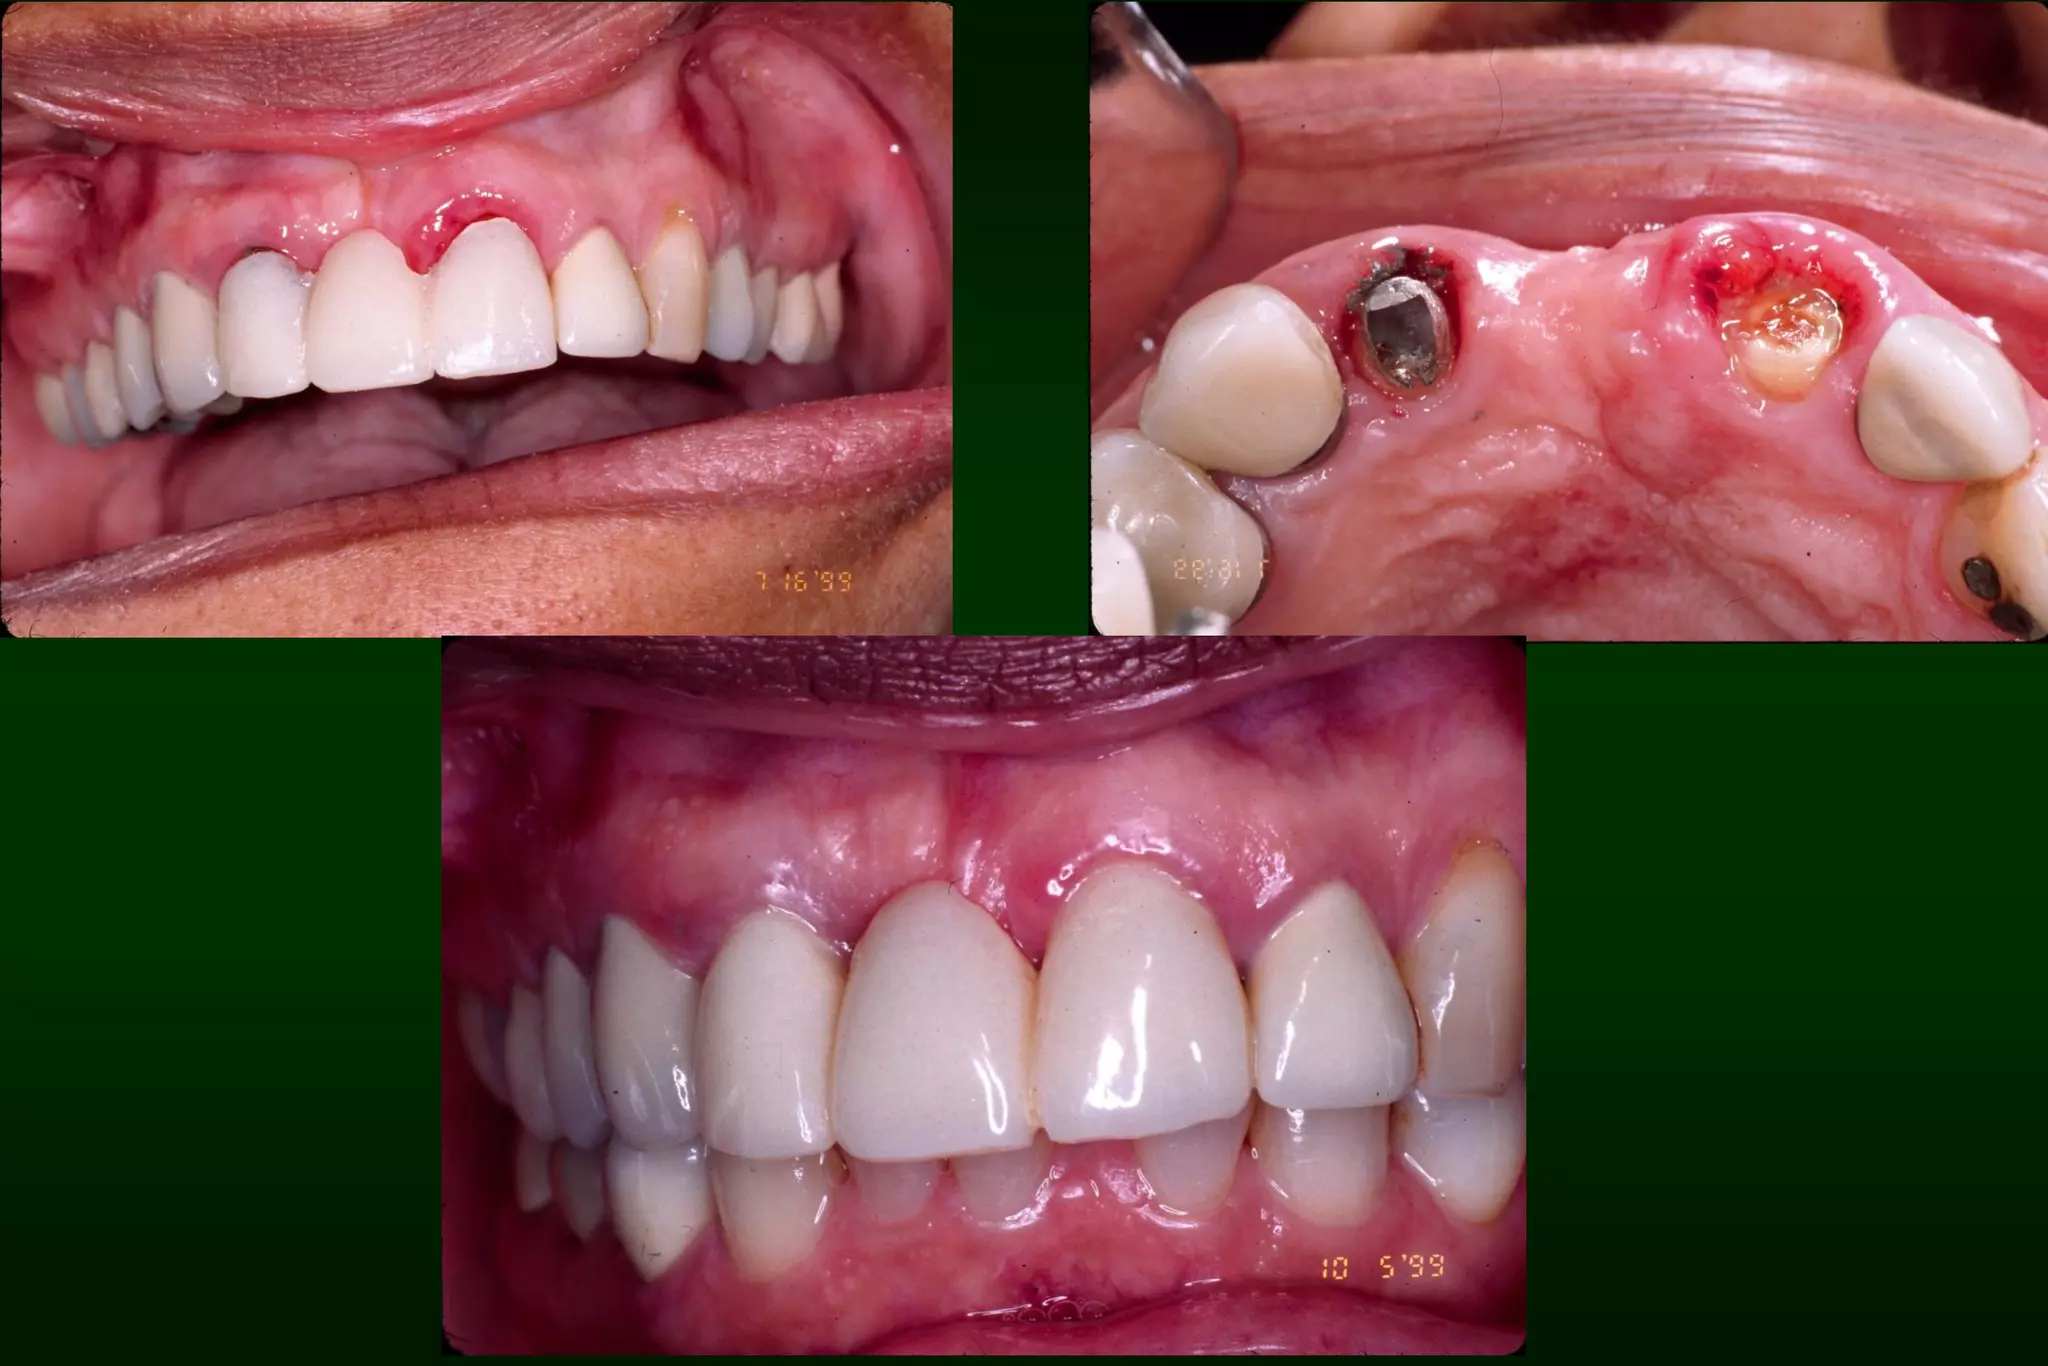

Types of Provisional Restoration II.Customized resin restorations 3. Indirect-direct (combination) technique 1. 2. 3. 4. 5. 6. 7. Advantages: Allows trial of esthetics, function and speech Provides template for the definitive restoration Ensures color stability Allows incorporation of reinforcement Saves chair time Permits removal and immediate replacement of nonsalvageable teeth Permits long-term treatment

Types of Provisional Restoration II.Customized resin restorations 3. Indirect-direct (combination) technique 1. 2. Indirect: polymerization of acrylic resin on mock preparation of teeth Direct: reline is performed intraorally

Permits removal and immediate replacement of nonsalvageable teeth

Permits long-term treatment